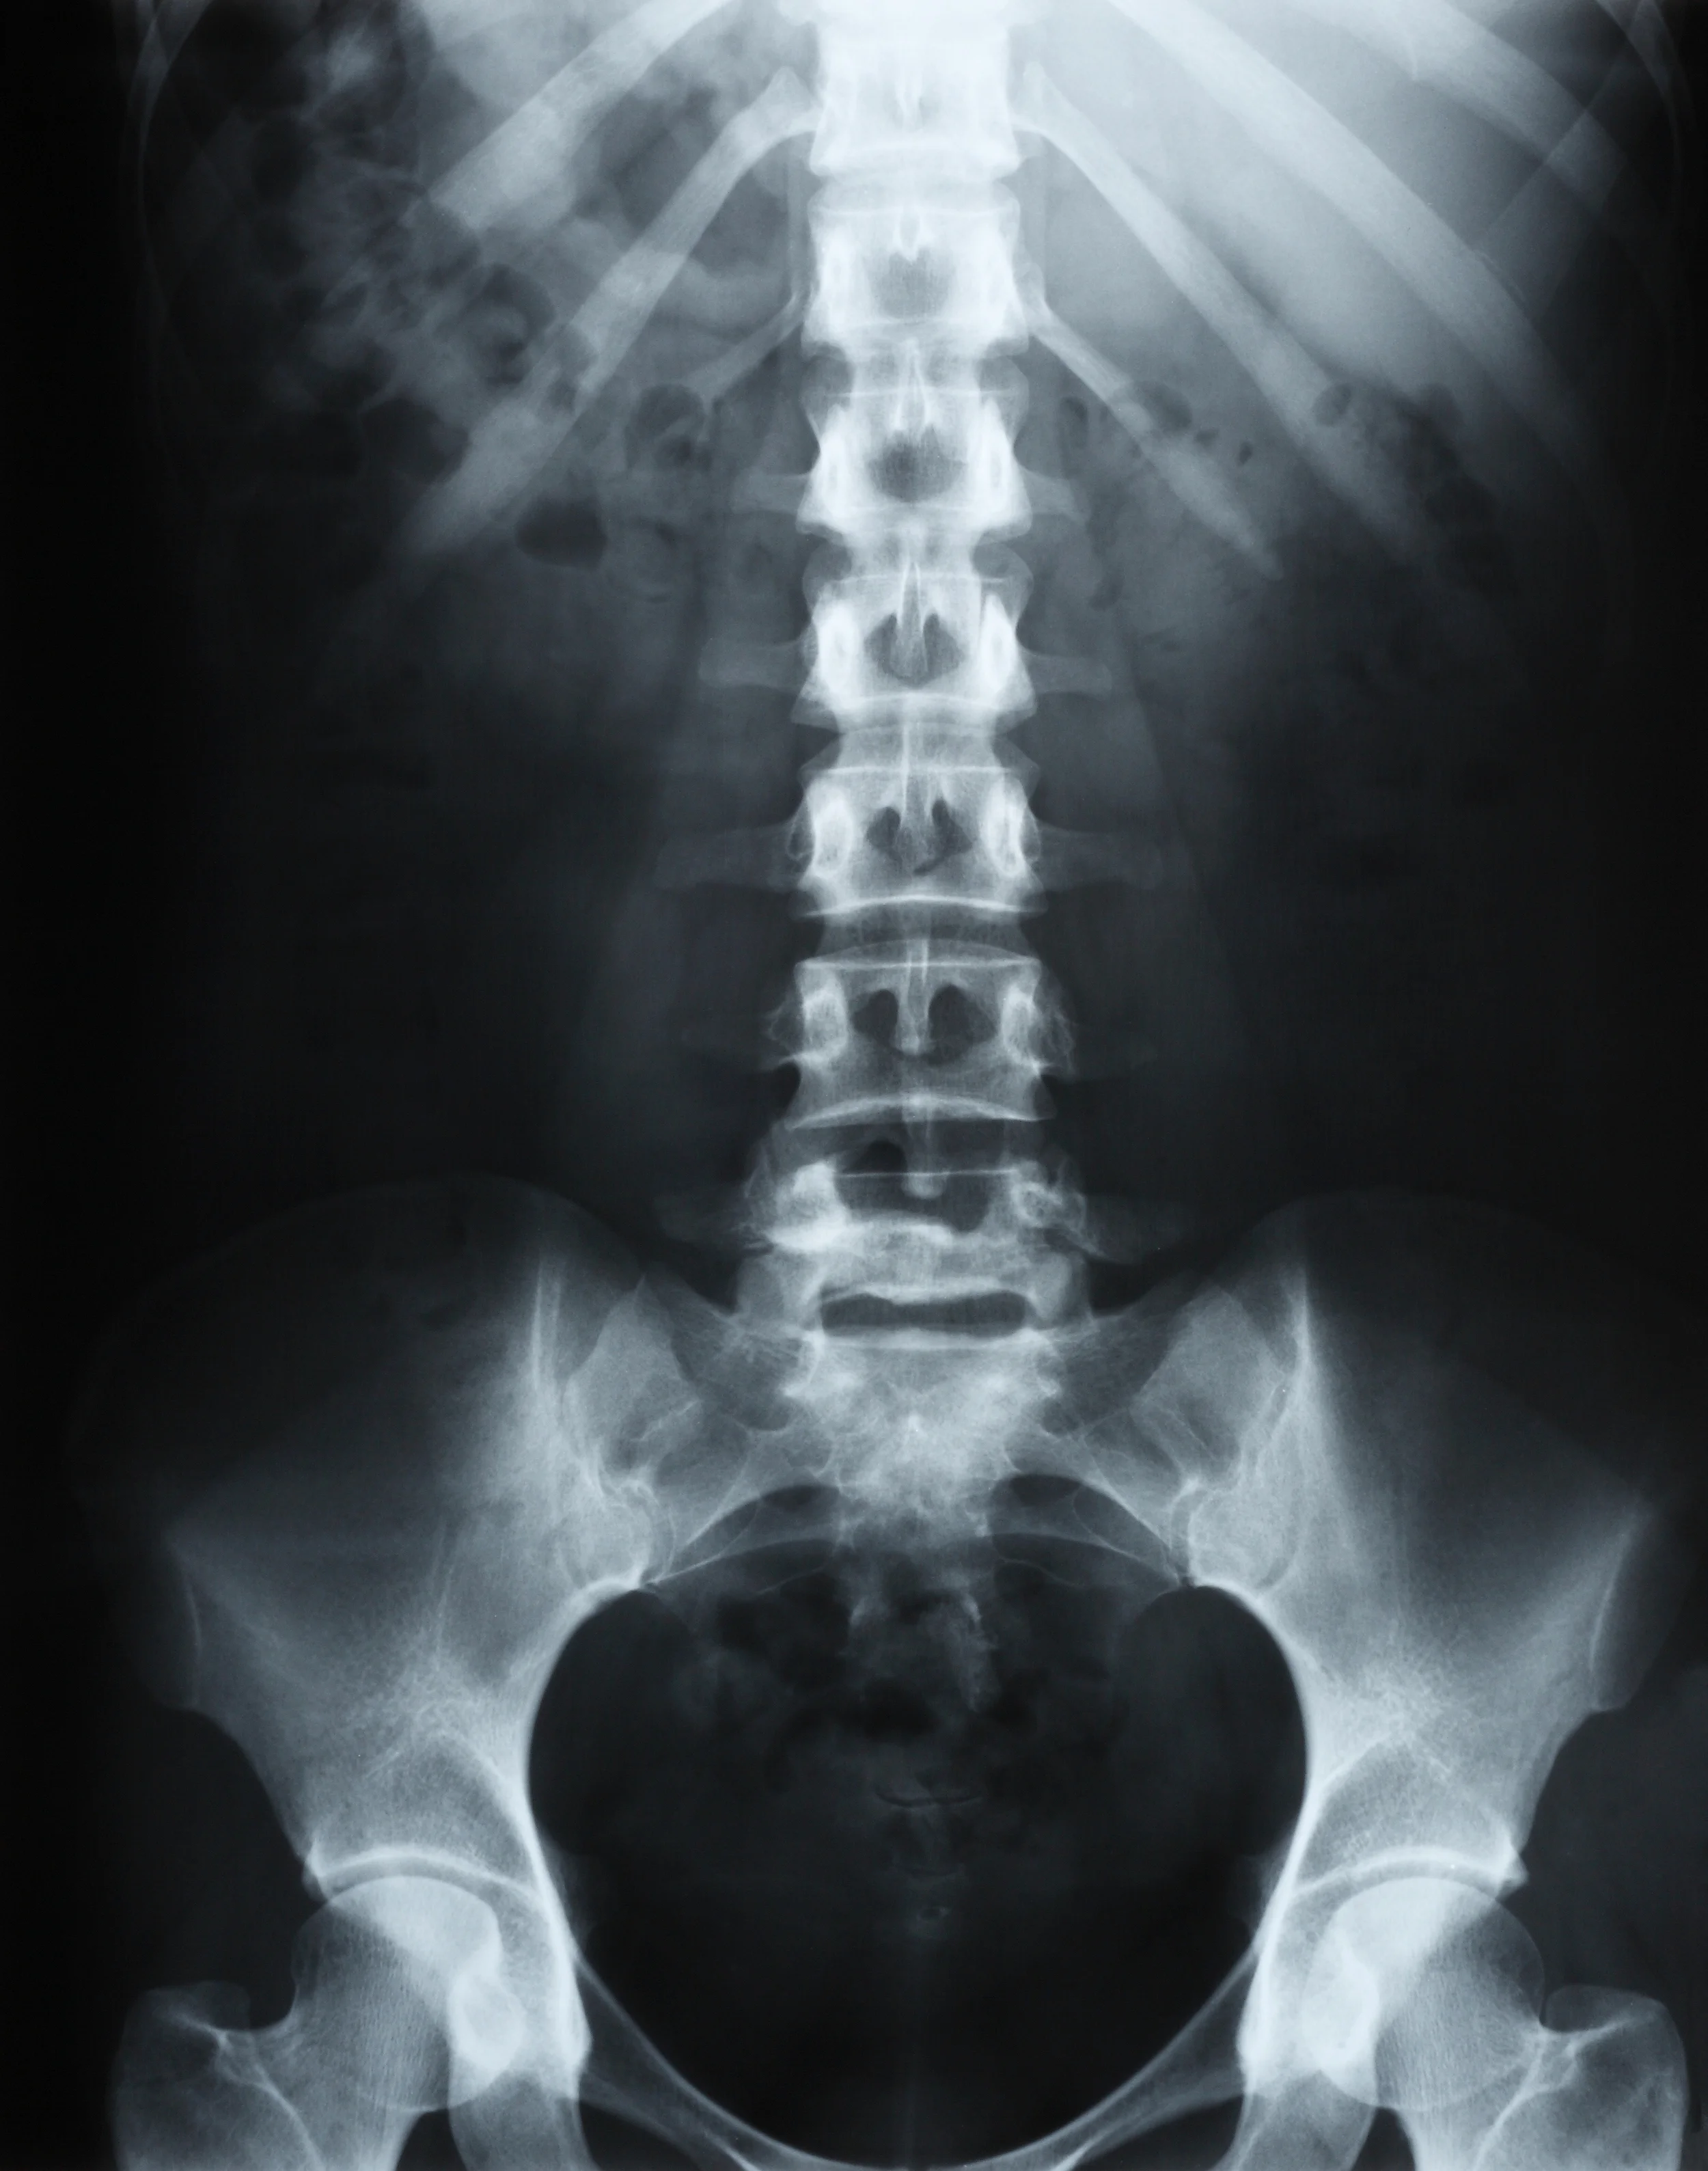

La lombalgie est une douleur située dans le bas du dos, au niveau des vertèbres lombaires. C'est le motif de consultation le plus fréquent en ostéopathie. Elle peut apparaître brutalement à la suite d'un faux mouvement ou s'installer progressivement, en lien avec des contraintes posturales, professionnelles ou sportives.

L'objectif est de comprendre les facteurs contribuant à la douleur, et non de se limiter à la zone douloureuse. Certains cas nécessitent un avis médical complémentaire ou des examens d'imagerie avant toute prise en charge manuelle.